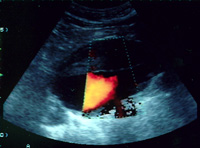

- ¿Que es el Doppler abdominal?

El Doppler pulsado, el Doppler color y el Angio-Doppler se utilizan en patología abdominal para:- Estudio complementario de masas hepáticas

- Evaluación del eje portoesplénico para el estudio de hipertensión portal

- Evaluación y seguimiento del transplante hepático y renal

- Estudio mesentérico para el estudio del dolor abdominal postingesta

- Evaluación de la actividad de la Enfermedad Inflamatoria Intestinal (Crohn)

- Diagnóstico de aneurisma disecante de la aorta abdominal

- Evaluación renal para el estudio de la hipertensión arterial

Debe realizarse siempre en ayunas.